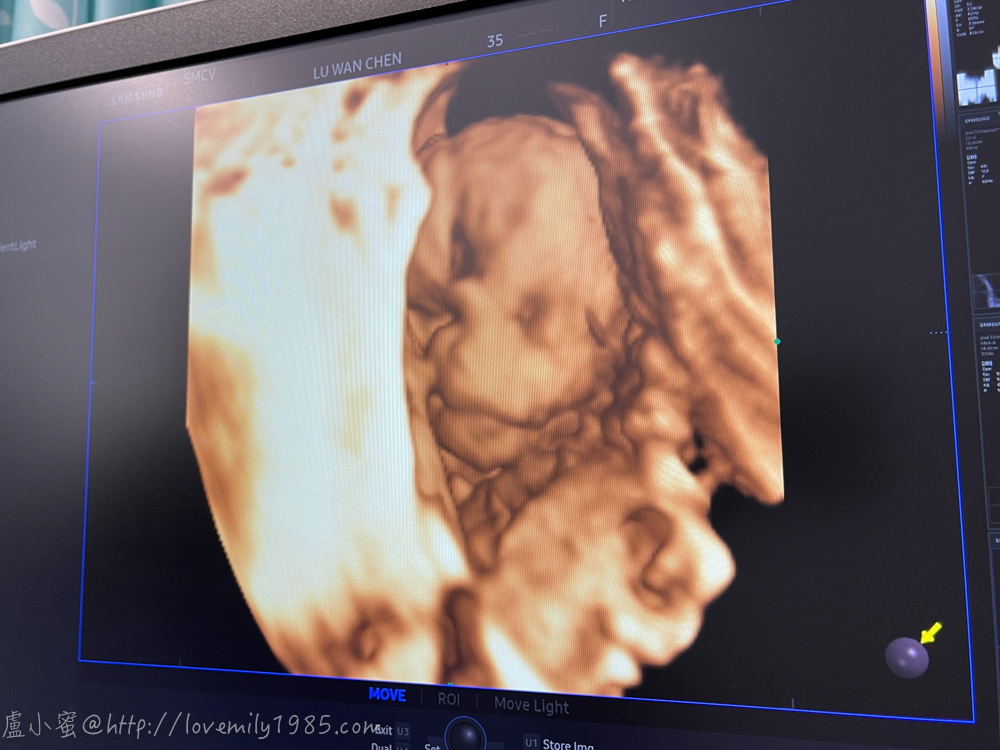

醫生說她藏起來了,又重新幫我定位重拍,這張有沒有比較明顯!

看得出來下巴、眼睛、鼻子,這是我們家三寶女娃,真神奇